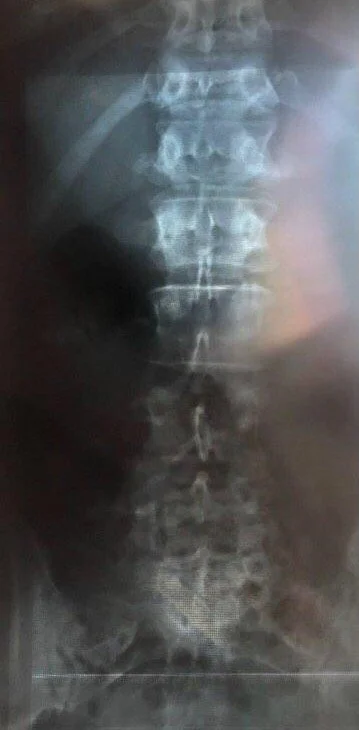

After utilizing Nathan Jelicic s non-manual, non-invasive therapy, new xrays were made and accompanying medical paperwork was issued to the patient based on those findings, dated 27.January.2020. (slightly over 1 month apart from the initial checkup)

X-ray lumbar spine in 2 planes with thoraco-lumbar transition from 27.01.2020.

Positioning of the lumbar spine and lower thoracic spine with regular alignment of the recorded vertebral bodies without height reduction or wedging. A significant scoliosis is not present. No significant narrowing of the intervertebral disc compartments.

Assessment:

• No evidence of spondylolisthesis, no significant scoliosis.

• No evidence of vertebral body wedging or fracture.